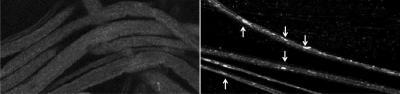

Materials move smoothly through the brain cells of a fruit fly larvae (left). But when scientists reduced the levels of the protein presenilin and the enzyme GSK-3B present in the nerve, tiny organic bubbles called vesicles began moving in an uncoordinated fashion and became trapped (right).

(Photo Credit: Shermali Gunawardena)